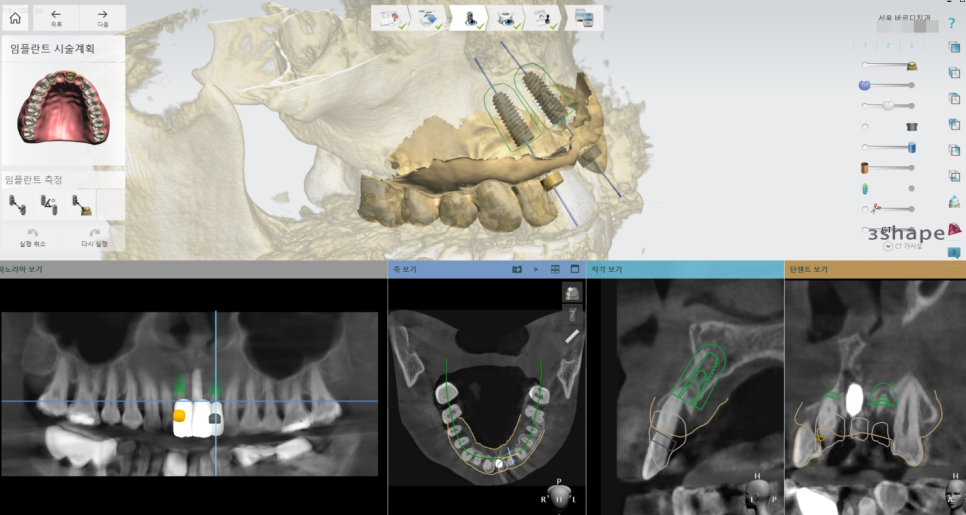

이런 난이도 높은 시술에서는

상일동역 치과가 보유한 장비를 활용하는데

네비게이션 임플란트 수술 기법을 적극 활용 합니다.

식립 각도, 사이즈

예상 보철 모양

치료 전후를 한눈에 볼 수 있기 때문에

너무 좋습니다.

수술 직후 사진입니다.

기존 임플란트 양 옆으로

임플란트를 식립

기존 임플란트가 없었더라면

2개만 심고 3개의 머리를 만드는 형태도 가능했겠지만

이미 치료가 되어있는 상태라

최대한 활용을 해주어야죠.

기존 임플란트에 손상을 주지 않는 선에서

치료를 계속 진행했습니다.